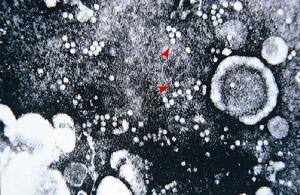

(1)病毒分離:是最早研究病毒的方法,其成功率取決於能否採集到含有足量 的活病毒樣品和找到敏感的組織。採集標本的時間最好在發病當天陽性率為86%, 6~10天採集陽性率下降至15%。標本為喉鼻、咽拭子或鼻洗液採集到的標本迅速 接種敏感細胞原代或傳代的上皮細胞如人胚腎、Hela、KB或HEp-2都對腺病毒敏感 ,病毒感染幾天至幾周后出現特徵性細胞病變病變出現的早晚因病毒的型別及病 毒的感染量而異。病變的特徵是細胞先變圓進而成球形並對光的折射增強許多病 變的細胞聚在一起似一串串葡萄。